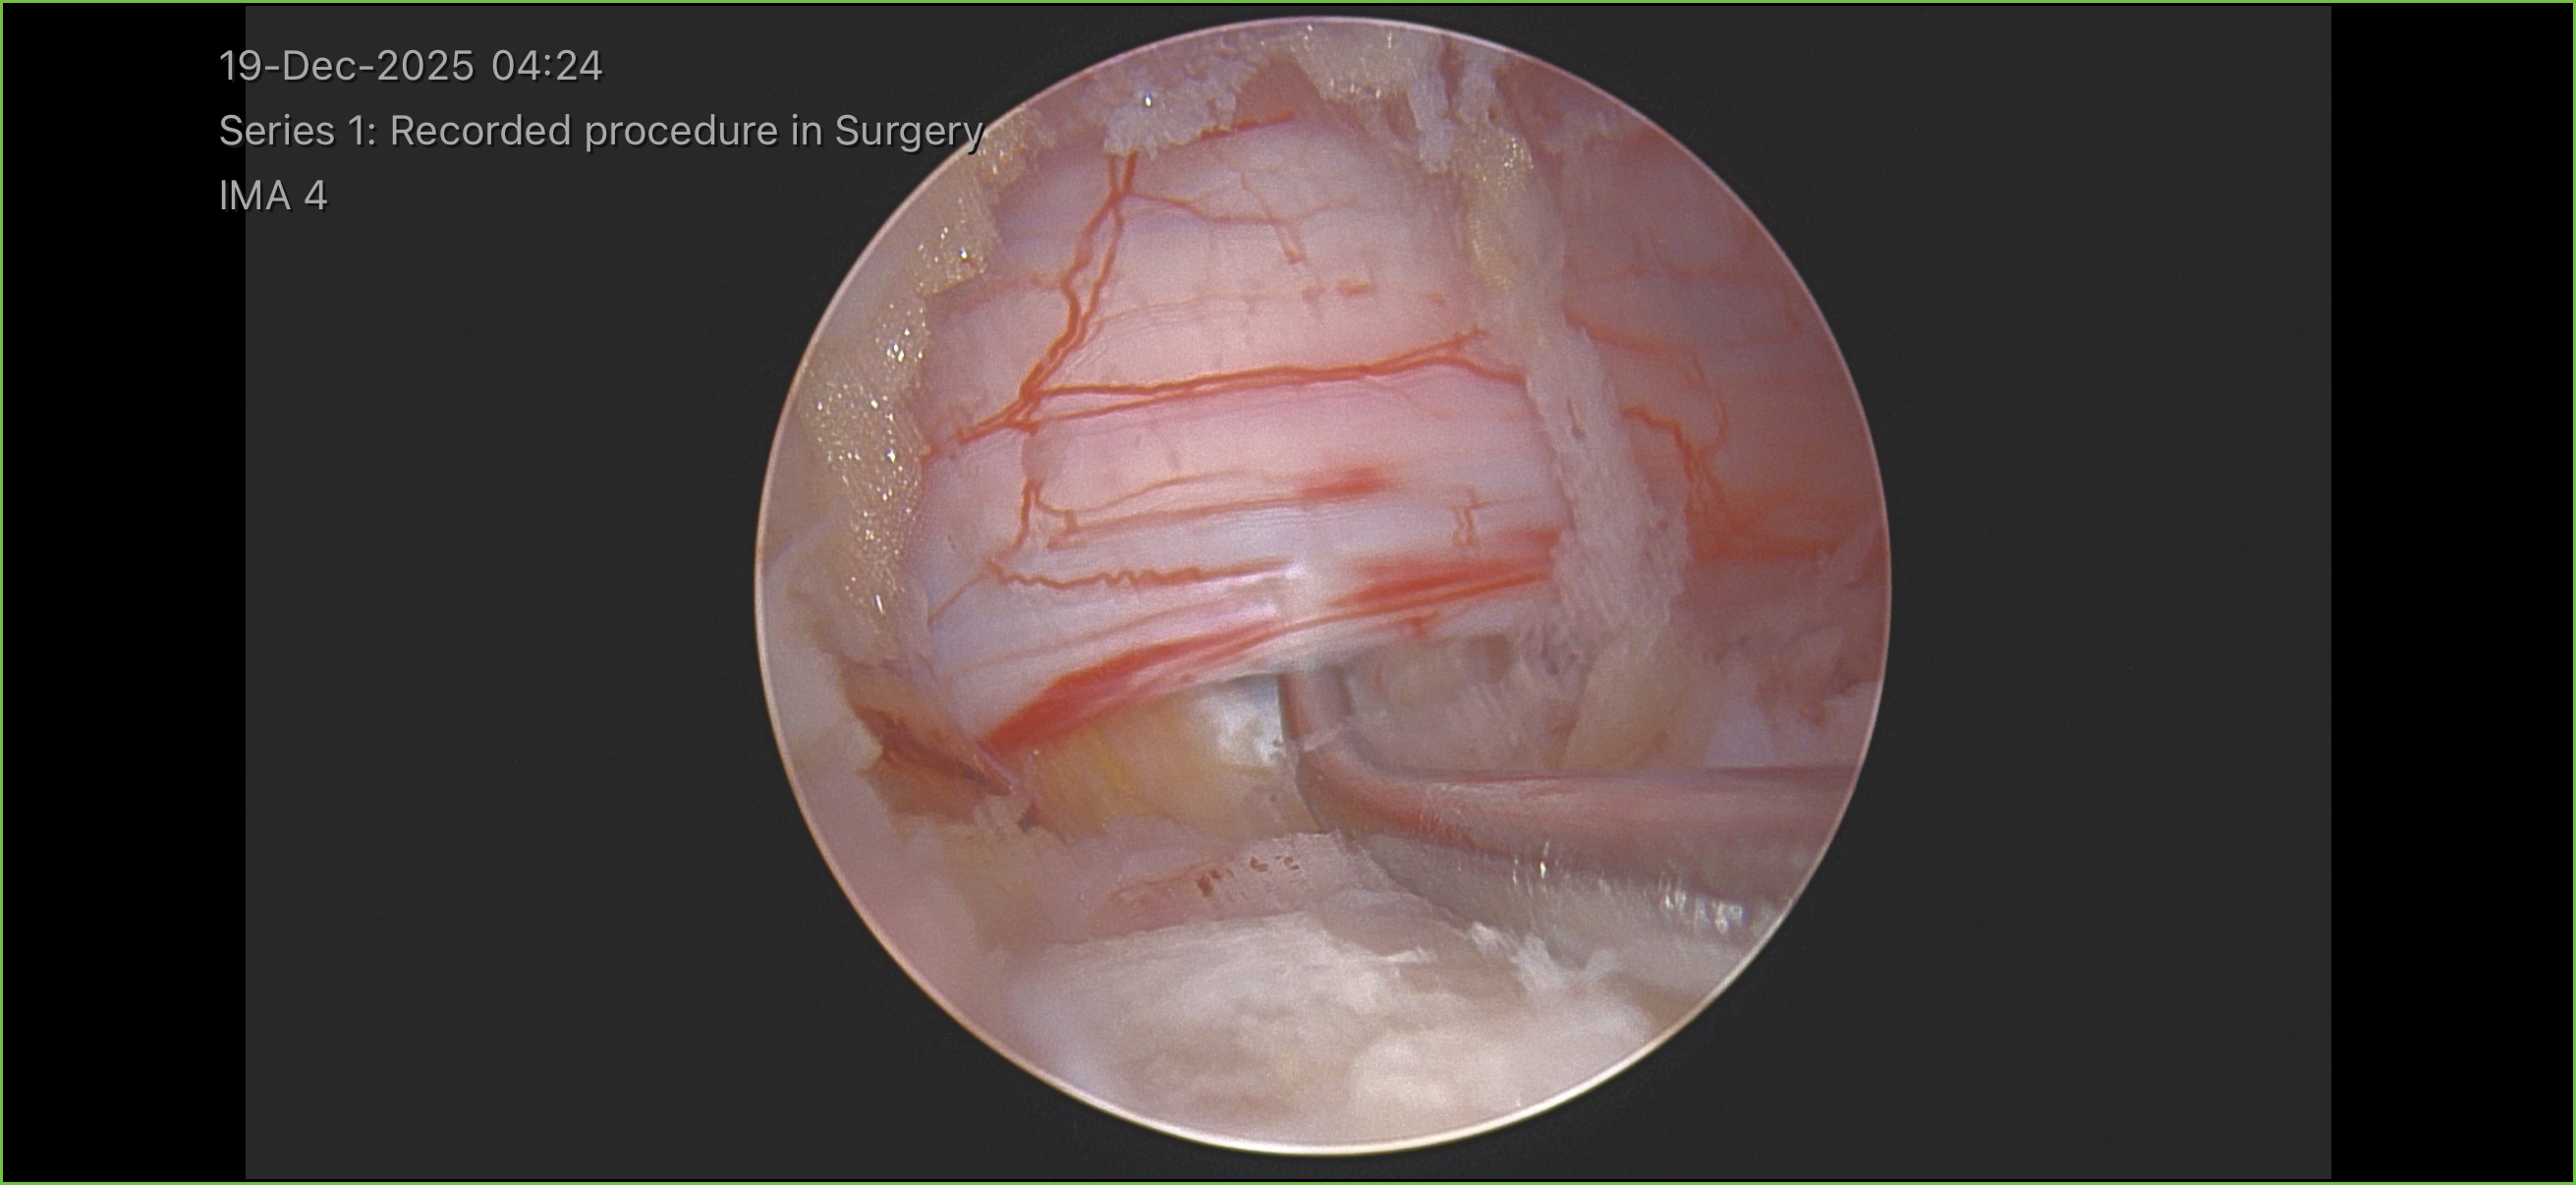

Images & Diagrams

Dr. Kazarian makes two small incisions (portals), each approximately 7 to 10 millimeters, near the affected area of your spine. One portal is used for the high-definition endoscopic camera, and the other is used for the surgical instruments. The muscles are gently dilated apart rather than cut, which greatly reduces tissue damage. This biportal technique provides Dr. Kazarian with an excellent view of the surgical area and full freedom of instrument movement, allowing greater precision than a single-portal approach.

Nerve Decompression

Using specialized micro-instruments through the instrument portal, Dr. Kazarian carefully removes the herniated disc fragment, bone spur, or thickened ligament that is compressing the spinal nerve while viewing the entire procedure through the camera portal. If a laminectomy is needed, a small portion of the lamina bone is precisely removed to widen the spinal canal. The high-definition endoscopic camera provides real-time visualization so Dr. Kazarian can protect the nerve root and surrounding structures with exceptional accuracy. The entire process typically takes 45 to 90 minutes.